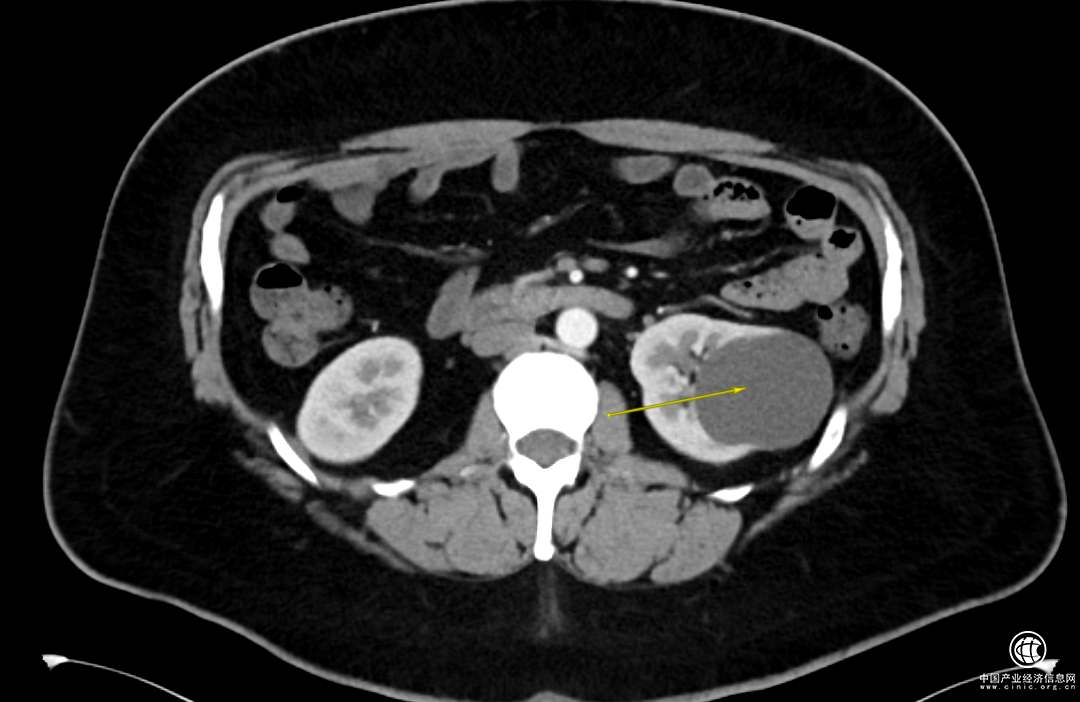

1個(gè)月前,Adam感覺到左側(cè)腰背部偶爾會(huì)有陣發(fā)性脹痛不適的情況,于是做了泌尿系彩超,發(fā)現(xiàn)左腎的囊腫已經(jīng)超過6cm了。

經(jīng)過一系列的檢查,詹紹洋主任診斷Adam是單純性腎囊腫,安排住院。

詹紹洋主任決定在全麻下行腹腔鏡下左腎囊腫去頂術(shù),將腎囊腫囊壁進(jìn)行切除,切除這部分囊壁后原先腎囊腫的完整性就被破壞,它的張力也就隨之消失,切除囊壁的腎臟部位就基本不會(huì)再次積聚囊液產(chǎn)生壓力從而再次形成囊腫。